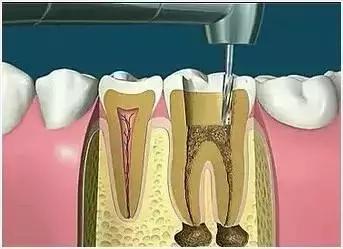

6、根管充填

封闭整个根管系统、堵塞主根管和侧副根管出口、防止微生物和液体的渗漏。无论是侧方加压法还是垂直加压法,应做到根管充填致密,根管充填后X光片上无根管腔隙,也不能超出根尖孔。